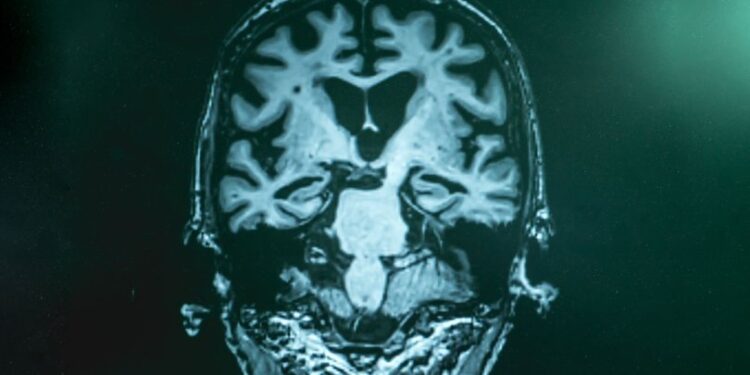

Alzheimer hastalığı, yıllar boyunca sinir hücreleri ve sinir bağlantılarına zarar vererek yavaş yavaş hafızayı ve diğer düşünme becerilerini hasara uğratıyor. Genellikle 60’lı yaşların ortalarında ortaya çıkan belirtiler, zamanla kötüleşerek ciddi zihinsel işlev kaybına neden oluyor. 65 yaş üzerinde 9 kişiden birinde görülen Alzheimer hastalığının yaş ilerledikçe sıklığı daha da artıyor.

Onlarca yıllık araştırmadan sonra, artık Alzheimer hastalığına bağlı hafıza problemlerinin, beyinde sessizce gelişen dejeneratif süreçlerin bir sonucu olduğunu biliyoruz. Dejeneratif süreçte önemli rol oynayan vücudumuza aldığımız toksin birikimi ve kontrolsüz şeker düzeyleridir. Bu süreçler, beyindeki amiloid ve tau proteinlerinin anormal birikiminden kaynaklanır ve bu protein kümeleri, Alzheimer hastalığının tanımlayıcı patolojik özellikleridir. İlk zamanlarda bu protein kümeleri ancak ölen hastaların beyinlerinde otopside tespit edilebiliyordu. Daha sonra, beyin görüntüleme yöntemleriyle amiloid ve tau birikiminin tespiti sağlanmaya başlandı. Şu anda, Alzheimer'ın teşhisi için artık, pozitron emisyon tomografi (PET) taramaları ve omurilik sıvısından alınan örneklerle amiloid ve tau proteinleri ölçülerek bir değerlendirme yapılıyor. Ancak, PET görüntüleme oldukça maliyetli ve radyoaktif madde içeriyor. Omurilik sıvısı testleri ise invaziv, karmaşık ve zaman alıcıdır.